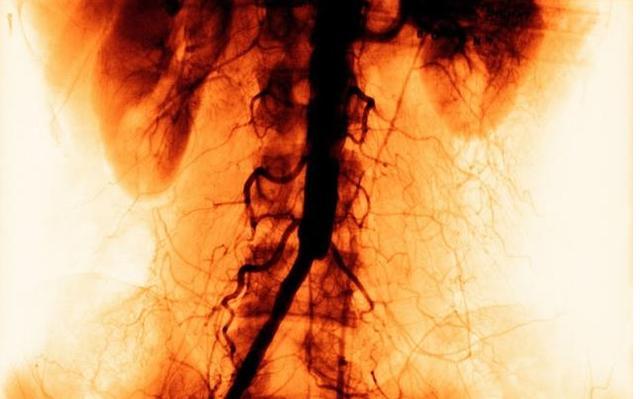

这条“青筋”能保命

有一个非常简单的方法,对于帮助防治脑血栓最是关键。值得一提的是,此方法不但简单,而且还可以自疗,有过脑血栓的患者也不妨一试,有益无害!

用刮痧板刮手指,尤其是两个手的中指及根部(青筋处)就可帮助防治脑血栓。

为什么刮青筋可防治脑血栓?

这是因为中指根部的这根青筋,一般代表脑部动脉硬化程度。

以左手为例,如果青筋出现在中指左侧(靠大拇指一侧),表示左侧动脉硬化、经络不通比较严重;此时,头部左侧容易出现不适;如果出现在右侧,则同理;如果两侧都有青筋,而且颜色较深,说明脑部的动脉硬化已非常明显。